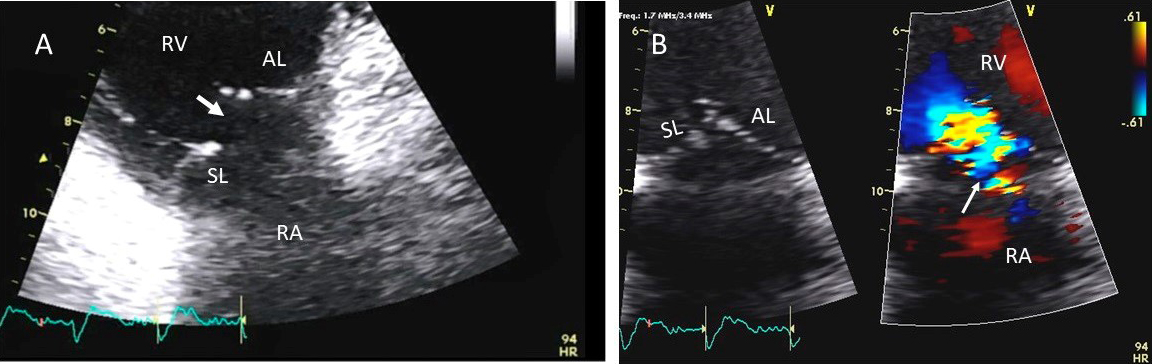

Examples of valvular injury directly from implantable cardioverter-defibrillator lead placement (Fig. 5A–C) or a permanent pacemaker (Fig. 6A–C) or endomyocardial biopsy in cardiac transplant recipients (Fig. 7A,B) are shown.

Fig. 6.Tricuspid regurgitation induced by pacemaker lead valve perforation. (A) Transthoracic 2D 4 chamber view showing pacemaker lead going through the TV leaflet (white arrow) and causing TR. (B) 3D enface view of the TV from the right atrial perspective showing the pacemaker lead going through the margin of the septal leaflet (SL) of the TV (white arrow). (C) 3D color Doppler view of the TV from the atrial perspective showing origin of TR at the site of leaflet perforation. MV, mitral valve; AV, aortic valve; PL, posterior leaflet; AL, anterior leaflet